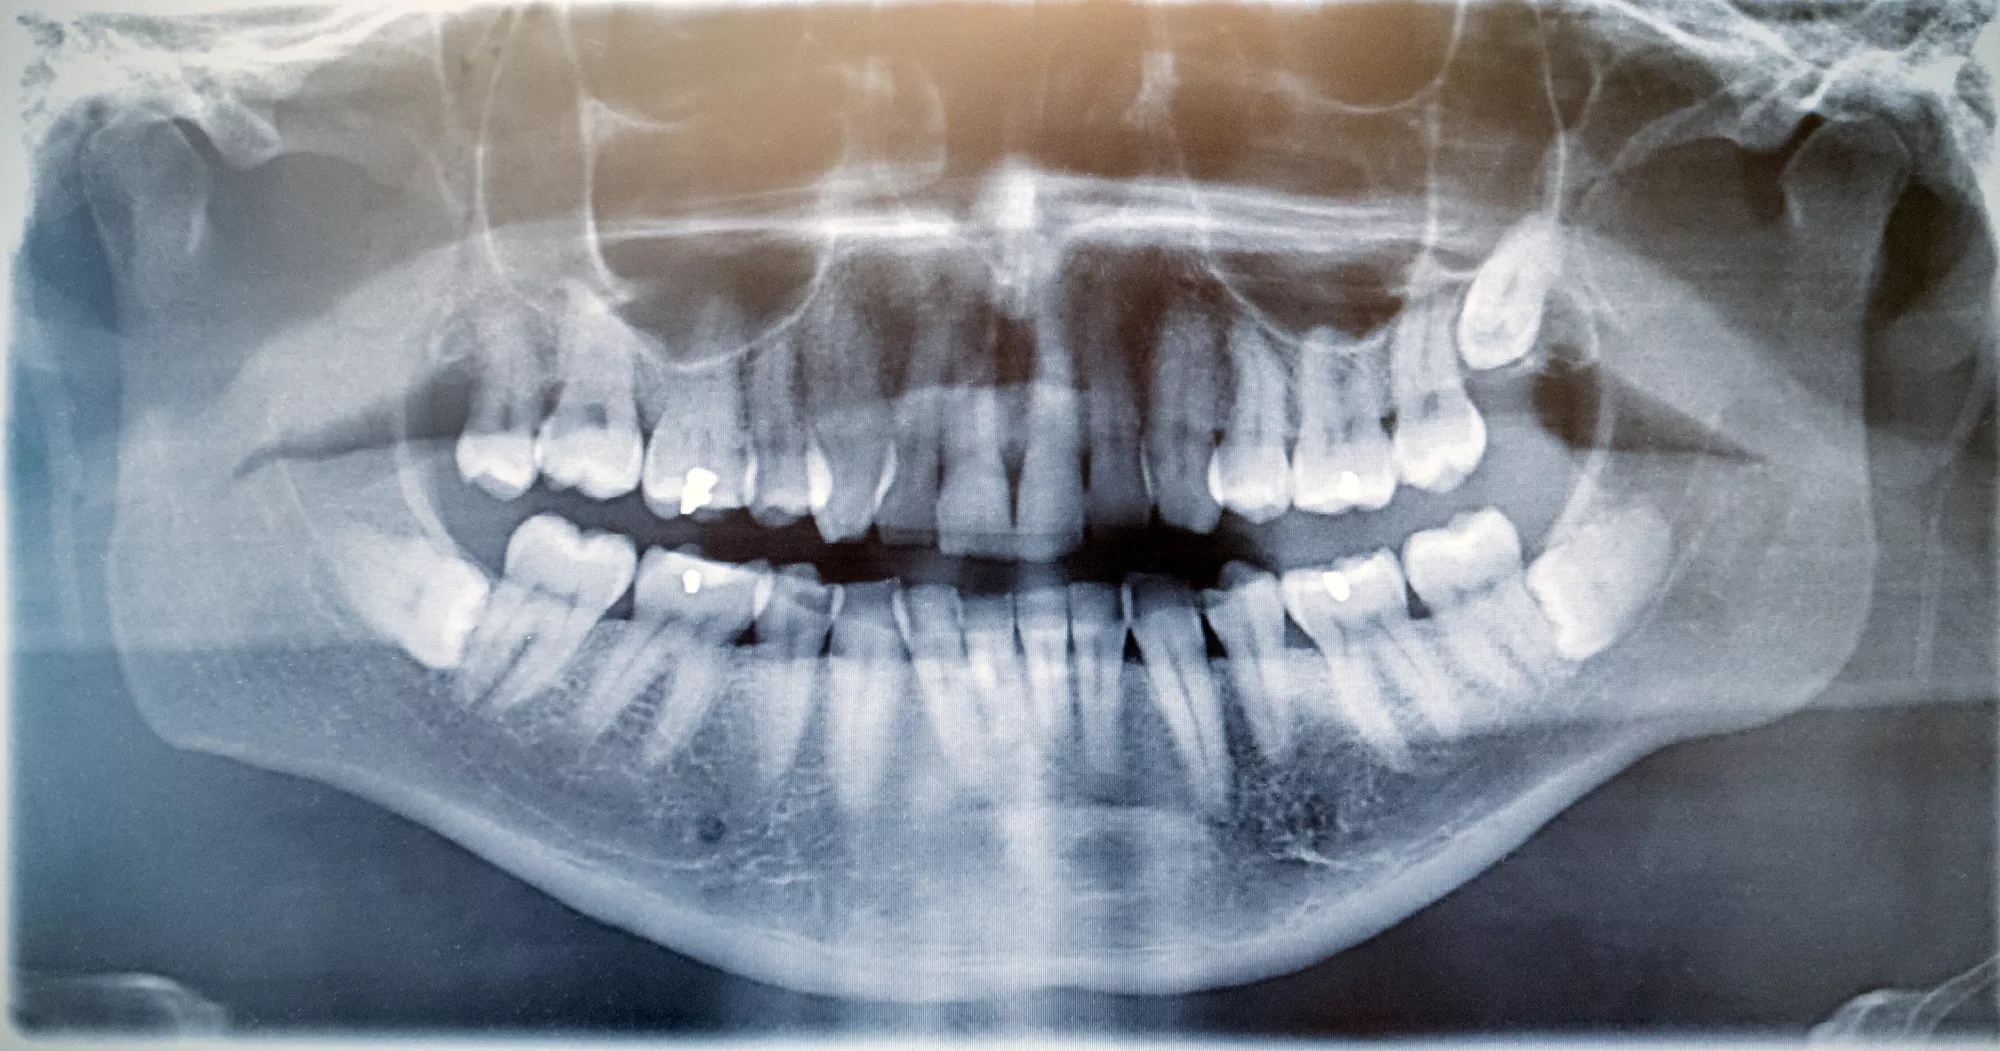

Early evaluation is important. At Foundation Dental Specialists, we use advanced imaging to assess the position of your wisdom teeth and determine whether removal is the best course of action.

At Foundation Dental Specialists, we use advanced dental technology—including high-resolution digital X-rays for precise imaging and modern sedation techniques—to make wisdom tooth extraction safer, faster, and more comfortable. Digital imaging allows us to clearly see the position of your wisdom teeth and surrounding structures, enabling more accurate treatment planning.